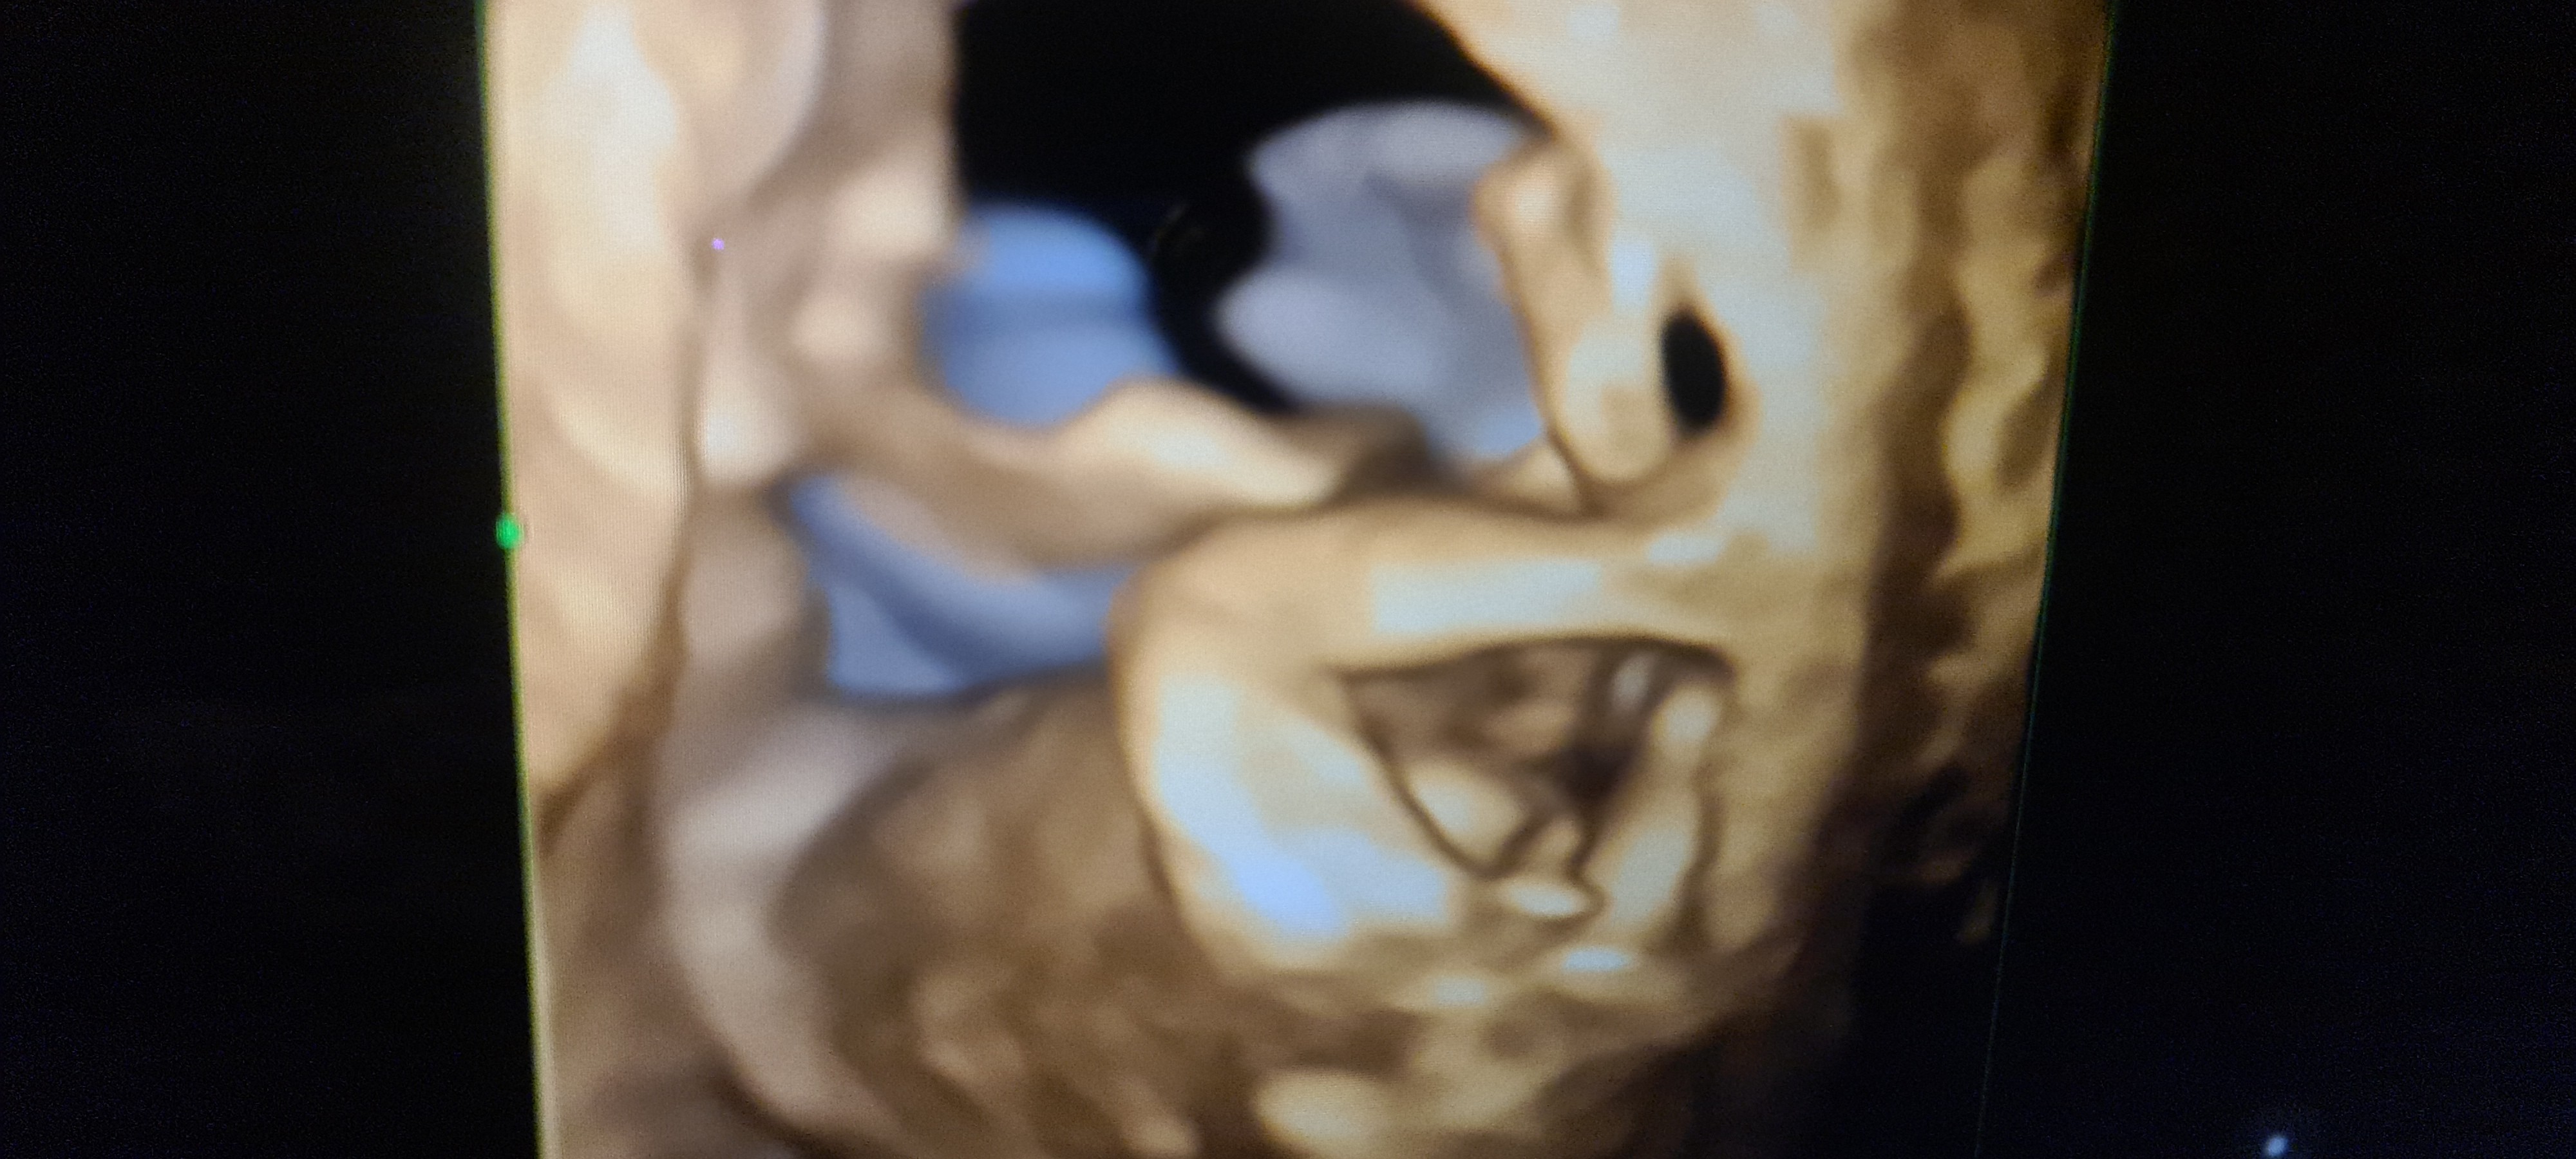

Dziewczyny, byłam na badaniu prenatalnym w 13tc i spytałam o płeć. Ginekolog przeznaczył na to 10 sekund po czym stwierdził - chyba chłopiec, ale może się zmienić. Ewidentnie widać, że coś odstaje, ale czy u dziewczynek w tym tygodniu wygląda to tak samo? Wstawiam zdjęcie mojego zdrowego dzidziusia i 2 z internetu jako porównanie. Już wariuję. Proszę o radę

Załączniki

• 20220113_214957.jpg

20220113_214957.jpg

1 MB · Wyświetleń: 150

• Screenshot_20220113-213706_Samsung Internet.jpg

Screenshot_20220113-213706_Samsung Internet.jpg

212,7 KB · Wyświetleń: 155

• Screenshot_20220113-190640_Samsung Internet.jpg

Screenshot_20220113-190640_Samsung Internet.jpg

158,2 KB · Wyświetleń: 155